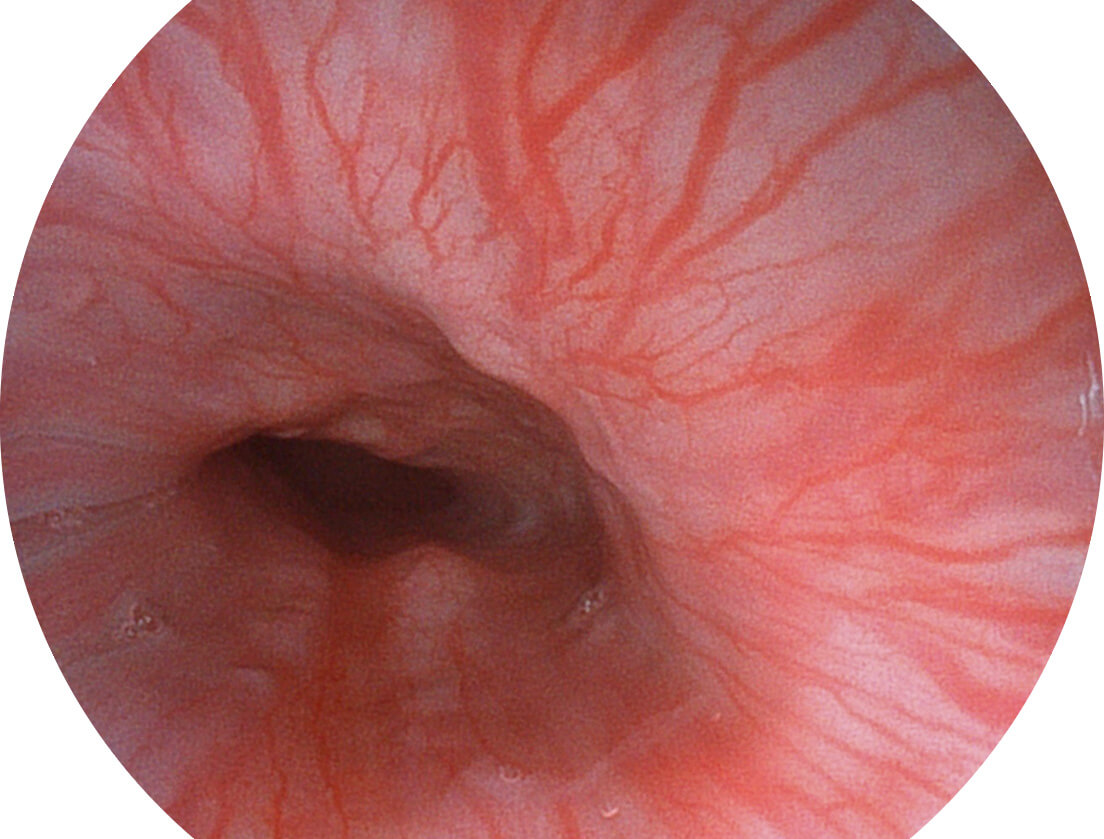

SFI图像

白光图像